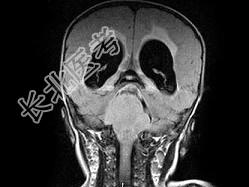

- 单项选择题男,2岁, 头痛、呕吐10余天,MRI检查如图所示, 最可能的诊断为 ( )

A、小脑蚓部髓母细胞瘤

B、星形细胞瘤

C、室管膜瘤

D、生殖细胞瘤

E、未见异常